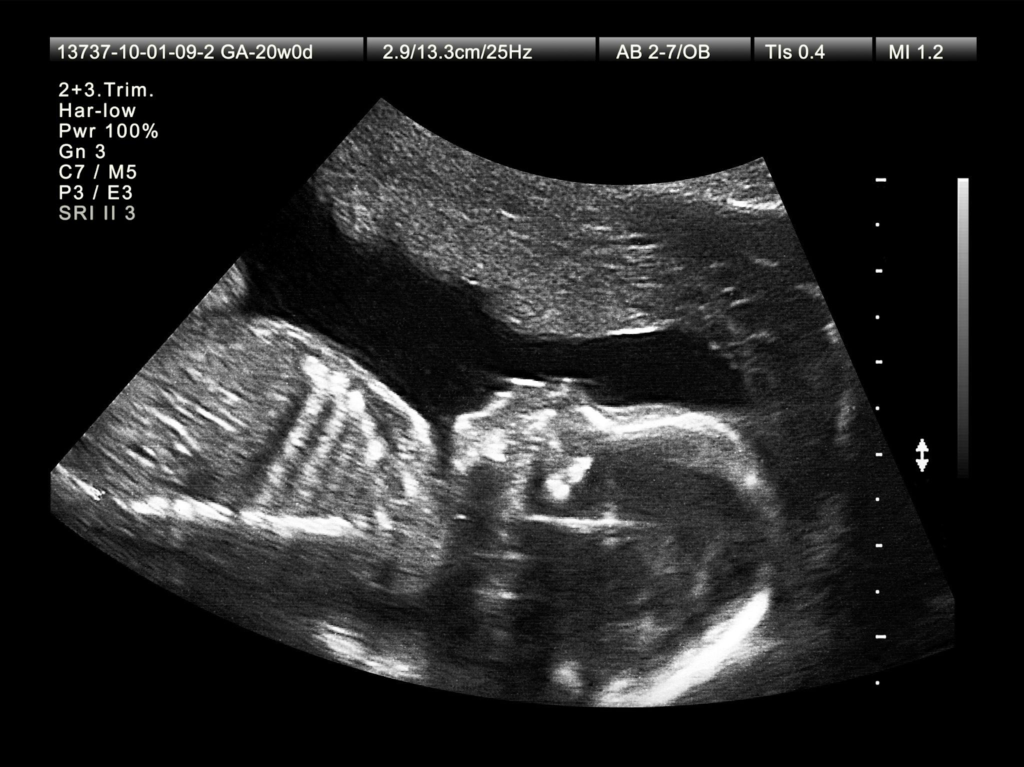

Do you think the baby is sleeping today? If you see that the baby is not moving at all for a few hours, then eat some sweet juice or a good meal and lie down on your left side. For an hour, observe whether the baby moves at least 3-4 times. If you still do not get a response, then that can be a big sign of danger signs of pregnancy in the second trimester. It is necessary to get an ultrasound or heartbeat check done quickly to see if there is any decrease in the baby’s life. The baby’s kick is the big proof that he is healthy.

In this middle period of pregnancy, your weight should also increase as your baby gains weight. But if you see that your weight is decreasing or not increasing at all, then that is a silent sign of danger signs of pregnancy in the second trimester. An ultrasound scan is needed to see if the baby is getting nutrition inside. Your worries and worries can hinder the baby’s development.

Importance of baby’s heartbeat and check-ups

Don’t wait for danger to come. Get a body check-up done at least once a month in Danger signs of pregnancy in second trimester. Knowing whether the baby’s heartbeat is normal or whether the amniotic fluid is normal can prevent many dangers in advance. Neglecting your body means playing with the future of your baby.